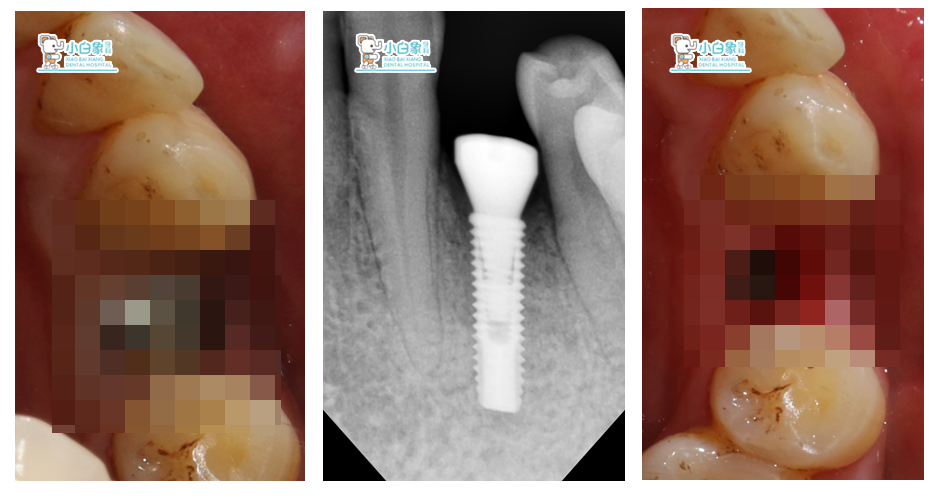

患者:***      男        43岁

初诊时间:2016年6月8日

结束时间:2017年3月25日

主诉:要求种植。

现病史:一月前,患者左下后牙松动脱落,就诊。

检查:颌面部未见异常,口内查:34缺失,牙槽骨低平,牙龈无红肿。

CBCT:34颊侧骨缺损。

诊断:下牙列缺损。

治疗方案:34植骨+美格真种植修复。

治疗过程:34必兰局麻下,切开翻瓣,在生理盐水冷却下,先锋钻,扩孔钻逐级备洞,植入美格真4.0*11.5mm种植体一枚,颊侧植骨+GBR,严密缝合。

2017年3月3日   34硅橡胶取模

基台+戴牙